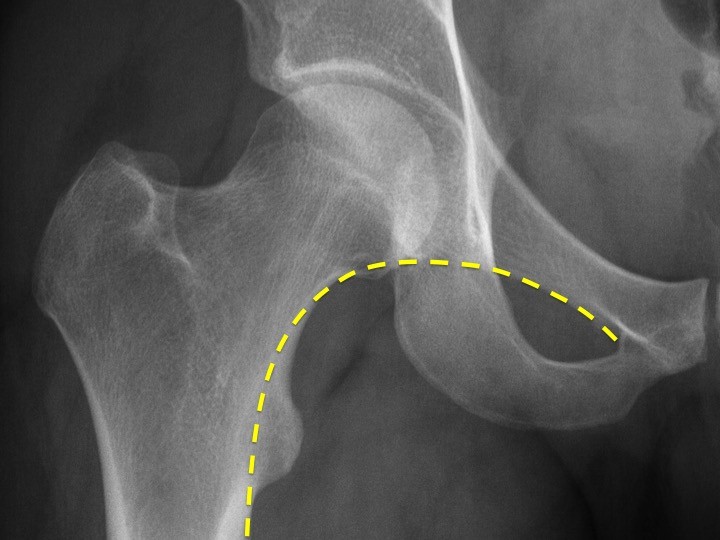

- Burada SHENTON ÇİZGİSİ önemli bir belirteçtir. Normalde femurun medialinden başlayıp pubis kolunun alt kısmına doğru düzgünce uzanır. Bu hattaki bozulmalar proksimal femur fraktürünü düşündürmelidir.

- Shenton’un haricinde femur başı, boynu, büyük ve küçük trochanterlerde kortikal hat düzgün olmalıdır.

- Trabeküler yapı da normal olarak karşılıklı olarak izlenmelidir.

- Shenton hattı, Kortekste, yada trabeküler yapıdaki bozulmalar proksimal femur fraktürünü düşündürmelidir.